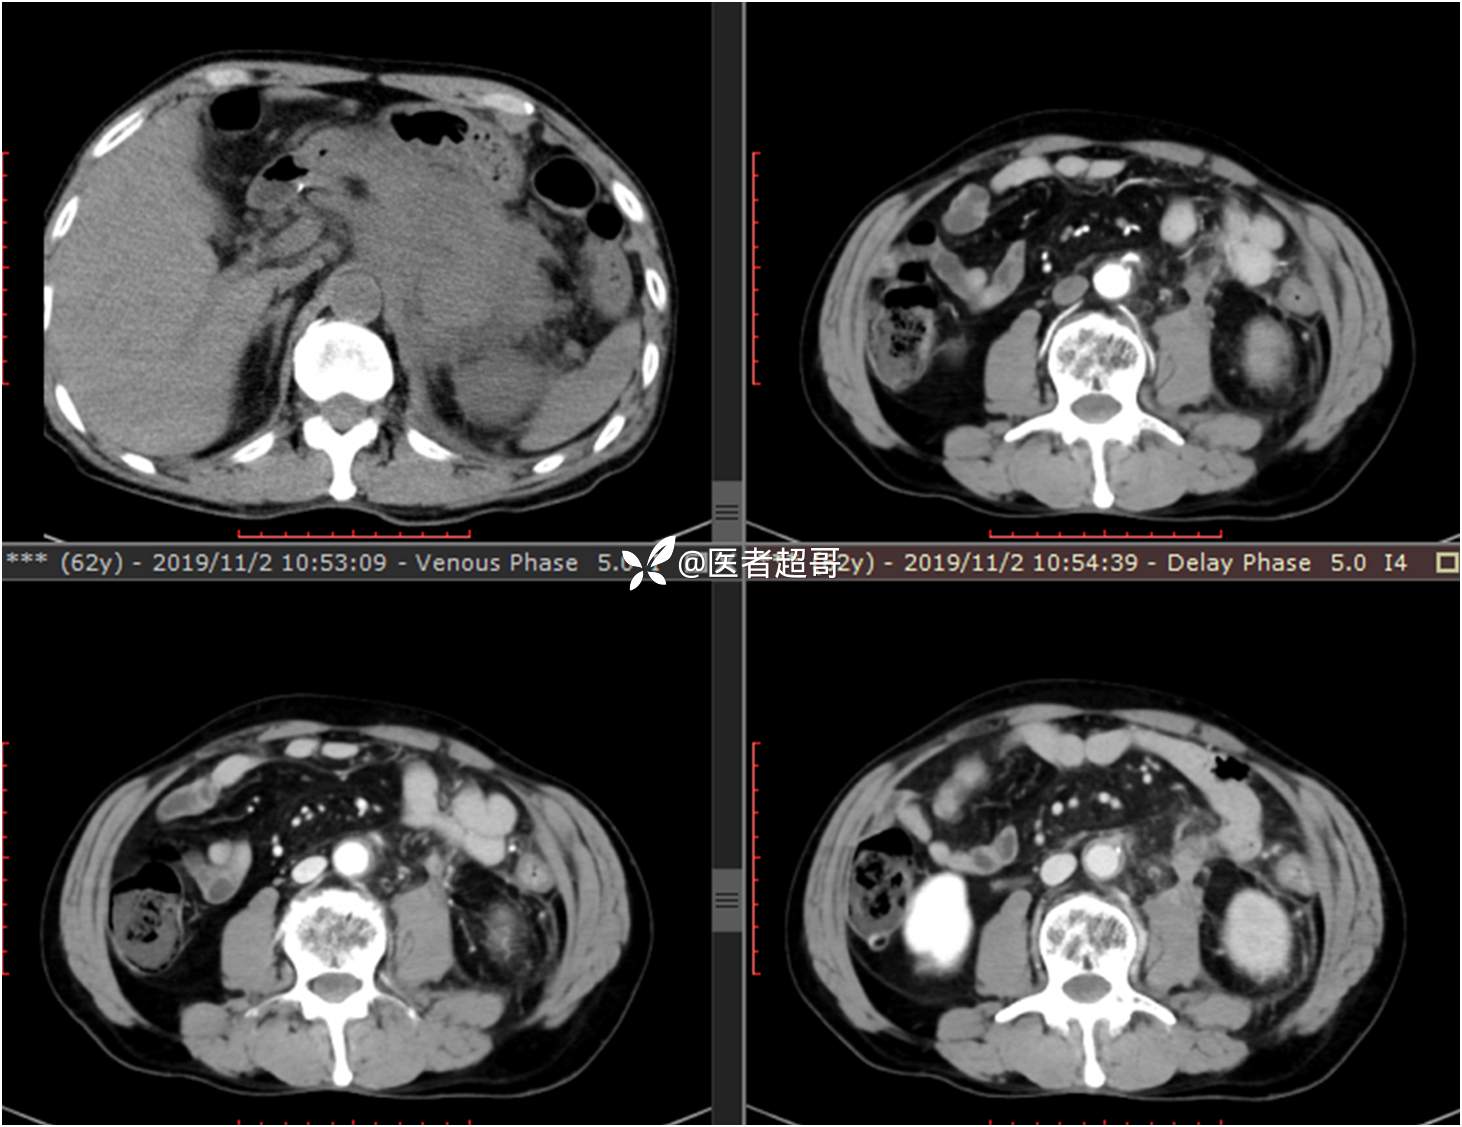

现病史:患者于1月前无明显原因及诱因出现左上腹部疼痛,为间断性疼痛,无恶心、呕吐,无寒战、高热,无腹胀、腹泻等伴随症状,在外未行特殊处理,患者于1周前自觉疼痛加重,为求诊治患者曾就诊于市东城医院,行全腹部强化CT提示:左肾上腺区肿块,符合恶性肿瘤侵犯左肾、胰腺及腹膜后大血管CT表现,行保守治疗,症状缓解,今患者为求进一步诊治,来我院就诊,行腹膜后占位穿刺活检病理提示:(腹膜后占位穿刺)小细胞背景内见细胞浆红染的神经节样细胞,建议到病理科加做免疫组化进一步明确诊断,遂以“腹膜后肿物”收入院,患者自发病以来,神志清,精神可,饮食、睡眠差,大小便正常,体重未见明显改变。